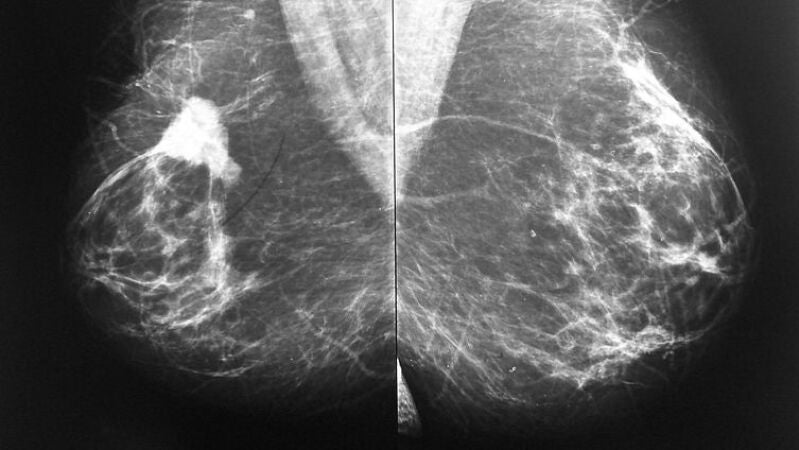

En una de cada cinco pacientes diagnosticadas concáncer de mamael tumor presenta sobre expresión de la proteínaHER2 que promueve la división celular y por tanto el crecimiento del tumor. Actualmente, son varios los fármacos que se utilizan para combatir esta proteína además de quimioterapia.